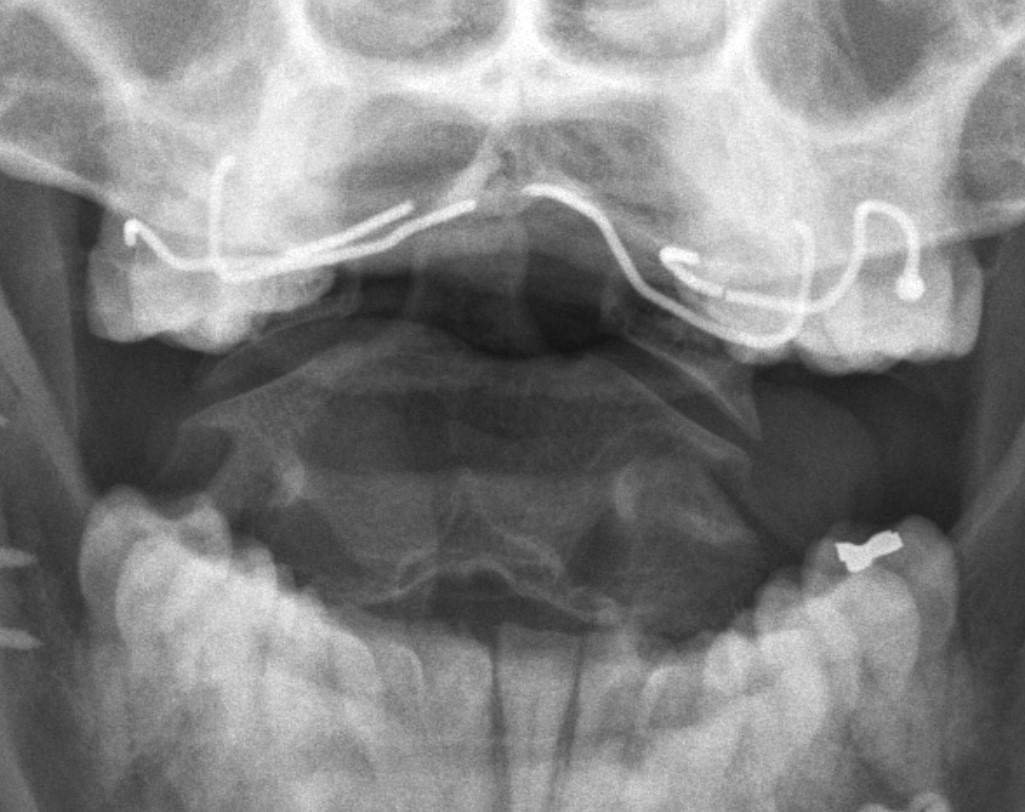

Deltoid ligament injury

Etiology

Ankle sprain

- eversion / external rotation

Ankle fractures